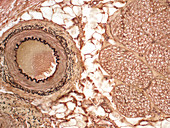

13296404 - Thickened muscular artery, light micrograph